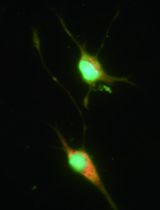

The human placenta is a highly specialized organ that is crucial for both maternal and fetal health during pregnancy. It is made up of highly branched villous tree-like structures that are bathed in maternal blood from approximately the 10th week of gestation (Jauniaux et al., 2000). Anchoring villi attach the placenta to the endometrium, which is transformed during placentation into the decidua. A population of fetal tissue-resident macrophages, the Hofbauer cells (HBC), are abundant within the stroma of placental villi. Early studies determined that these cells are of fetal origin based on Y-chromosome detection in pregnancies with male fetuses (Kim et al., 2008). HBC are the only immune cell population on the fetal side of the placental barrier in the steady-state (Thomas et al., 2021). Accordingly, they are thought to have important roles in the regulation of placental growth and homeostasis and to act as immune sentinels, protecting the fetus from infection in utero. However, compared to other adult tissue-resident macrophages, HBC remain poorly understood. A range of protocols has been used to isolate HBC, as excellently reviewed elsewhere (Tang et al., 2011). However, a standard technique has not been established across the field. Many of the protocols used are suboptimal for the isolation of tissue macrophages. For example, unnecessarily long digestion times (sometimes up to 3 h) and the failure to use DNase I greatly affect HBC viability. Furthermore, HBC are typically isolated as total CD14+ cells from placental tissue for phenotypic and functional analysis. However, we have previously shown that maternal cells can comprise up to 30% of CD14+ cells isolated from first-trimester placental digests (Thomas et al., 2021). By adding common HLA allotype antibodies to our flow cytometry panel, we can distinguish maternal from fetal cells and ensure the isolation of a pure population of HBC. Therefore, in all future research of HBC using in vitro assays, additional steps that are described here should be performed to ensure that true fetally-derived HBC are studied with optimal viability.

In this article, we provide step-by-step protocols to isolate HBC from first-trimester and full-term human placental tissue with high purity. Procedures B and C describe how to obtain single-cell suspensions from first-trimester and full-term placental tissue, respectively. Procedure D describes how to obtain HBC from placental digests with high purity by fluorescence-activated cell sorting (FACS). Following these protocols allows investigating HBC properties with downstream in vitro assays to understand their functional properties further. A scheme of the overall procedure of HBC isolation from first-trimester and full-term placenta is shown in Figure 1.

Figure 1. Isolation of HBC from human placenta. A schematic outlining the procedure for isolating HBC from first-trimester and full-term placenta.